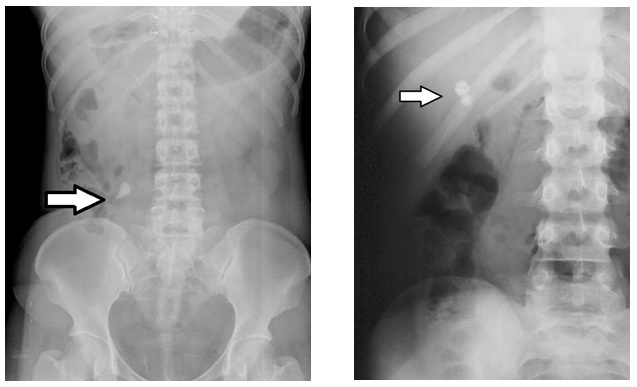

Cálculo renal radiotransparente, que não aparece em Rx simple de abdome? Fatores de risco e tratamento?

Ácido úrico

FR: hiperuricosúria (pH <5 ácido), gota

Tratamento crônico: ingesta hidrica > 2,5L/dia, dieta com restrição de purinas (frutos do mar, carne vermelha, cerveja), citrato de potássio (alcaliniza urina), alopurinol

Locais de maior obstrução de calculo renal?

Pontos de constricção do ureter:

JUP (junção uretero-pélvica)

JUV (junção uretero-vesical)

1/3 médio (cruzamento com vasos ilíacos)

Paciente com dor lombar de inicio agudo, principalmente em flonco, com irradiação para baixo-ventre (saco escrotal ou grandes labios), associado a hematuria, nauseas, vômitos, sudorese…

Diagnósticos, exame padrão ouro, complicações, tratamento agudo…

NEFROLITÍASE

Hematúria: sintoma mais comum

Complicações: infecção, anúria (IRA pós renal)

Exame padrão-ouro: TC sem contraste de abdome (hiperdensidade)

… USG trato urinário (imagem hiperecogênica com sombra acustica posterior)

Tratamento agudo: analgesia, AINES +/- opioide, antieméticos, alfabloqueador (tansulosina) se < 1cm, evitar desidratação, avaliar intervenção (> 1 cm)